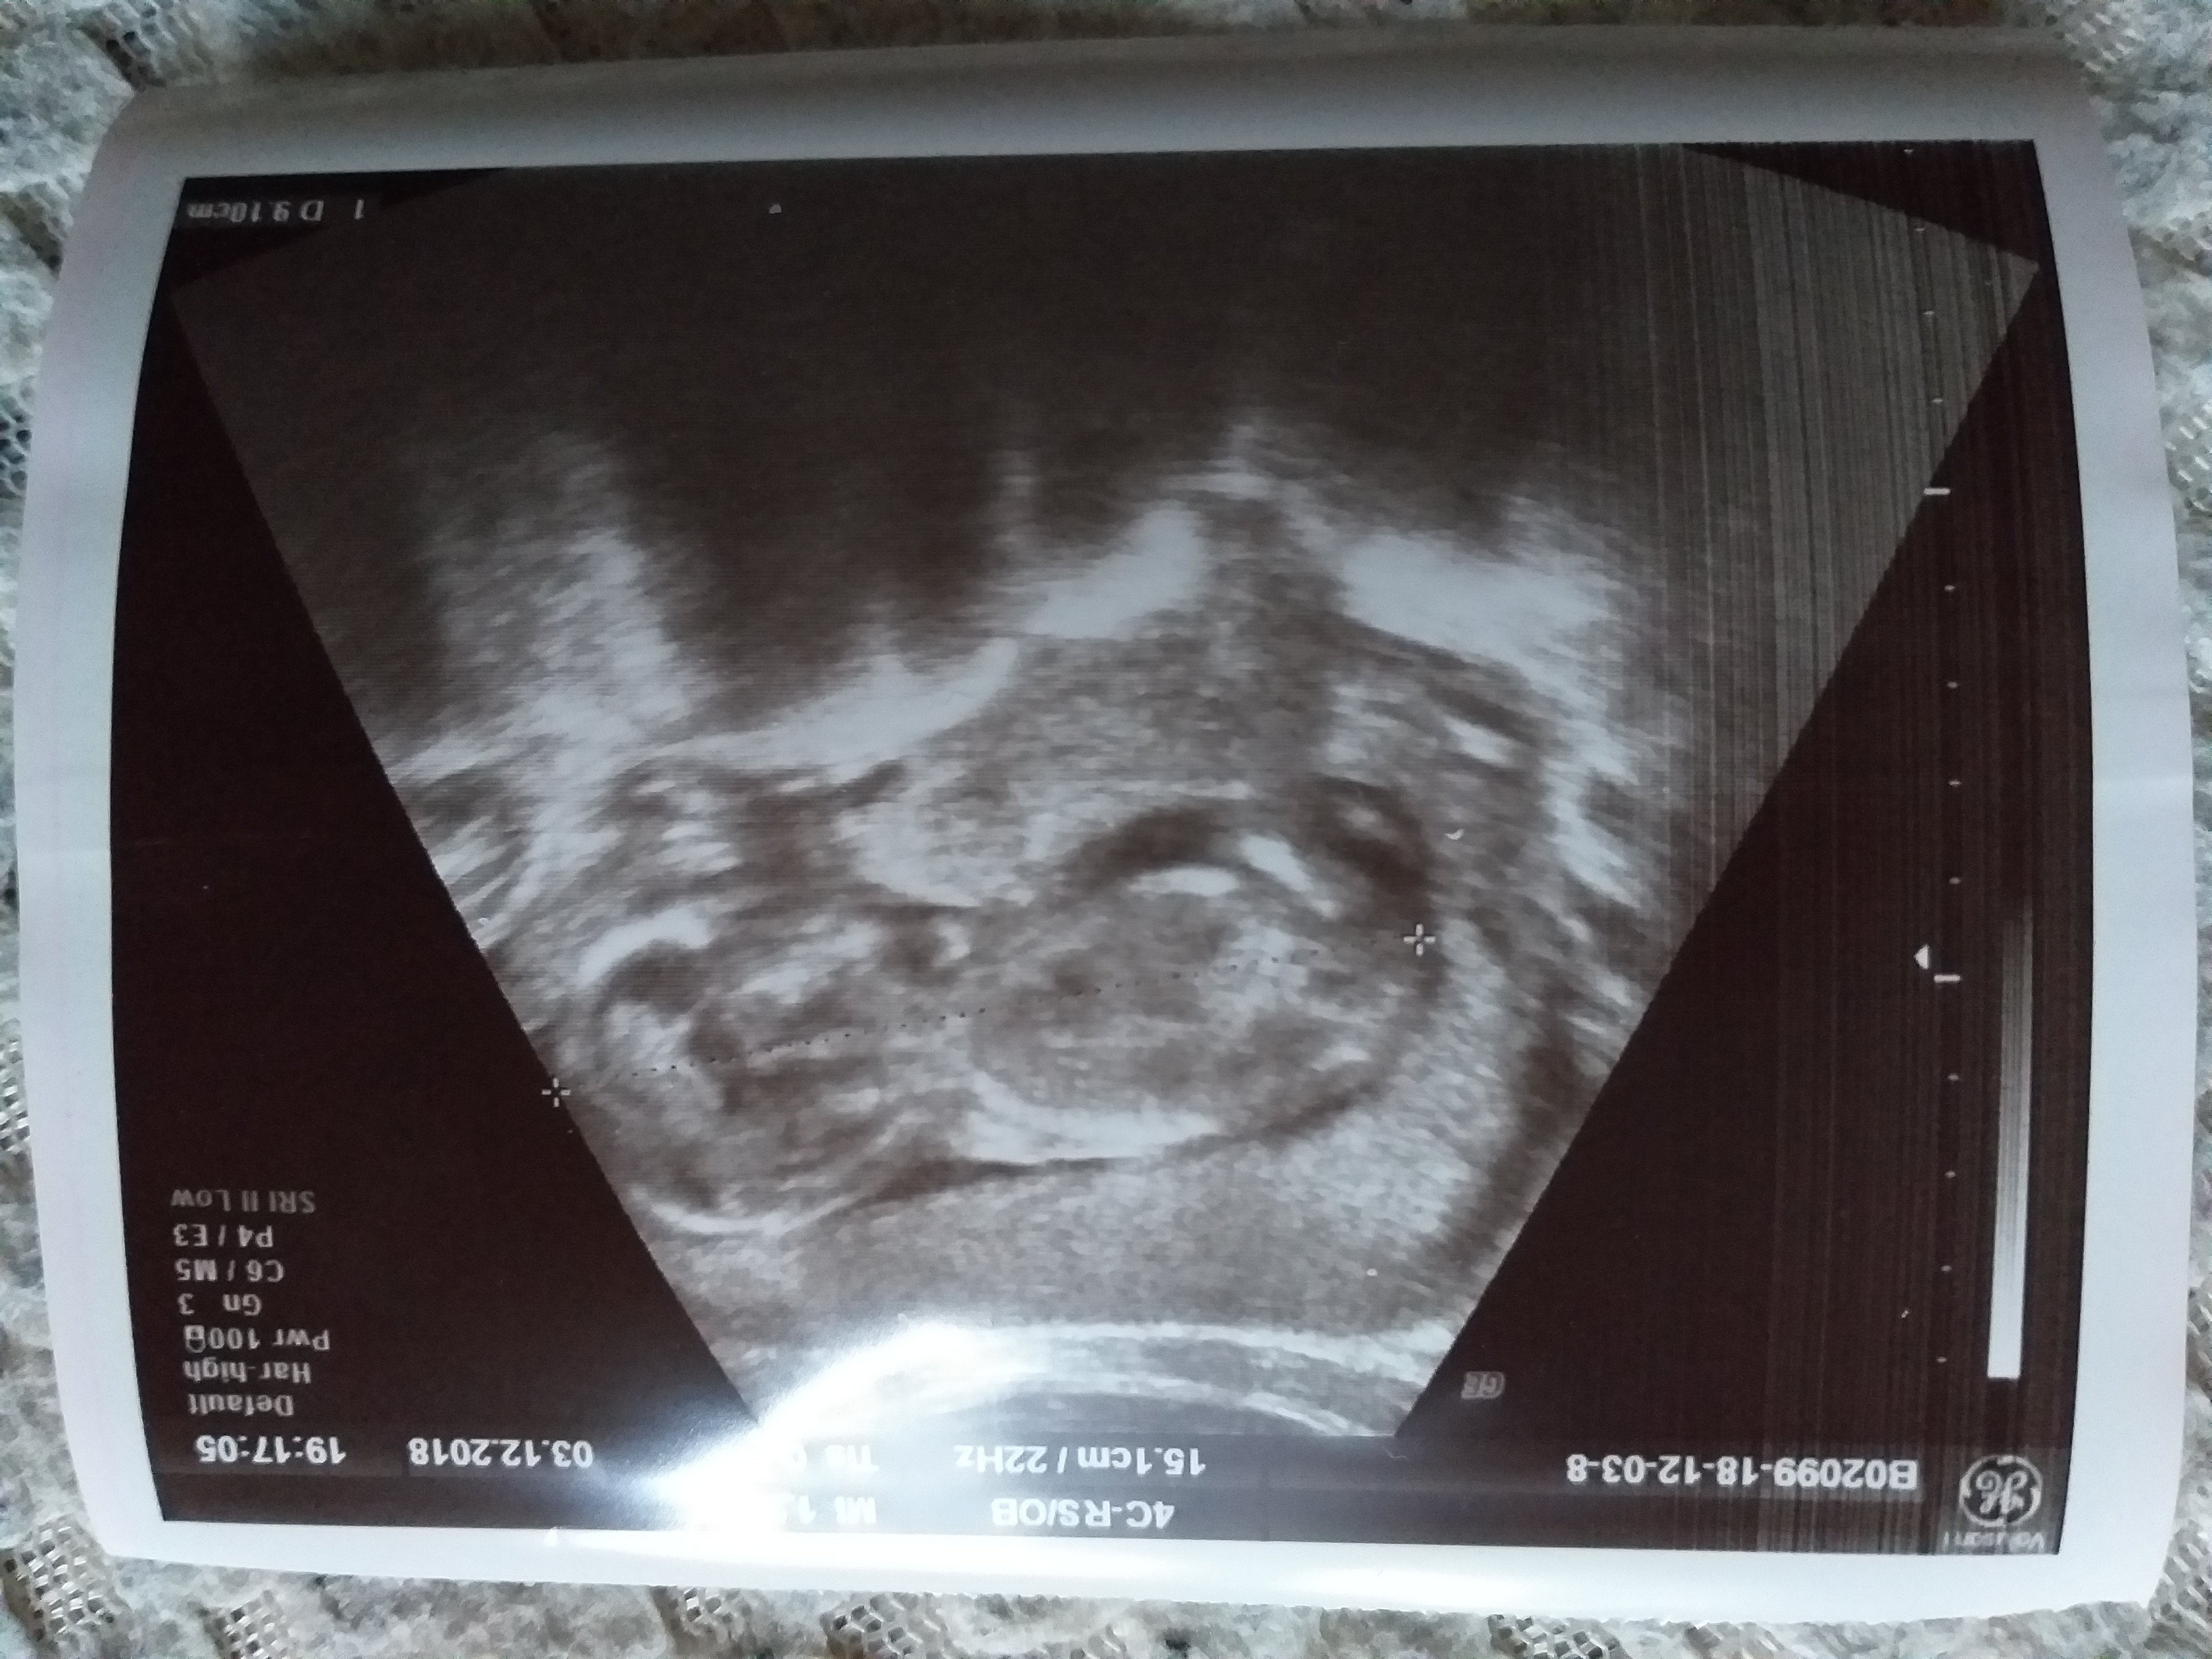

Miałam wczoraj wam pisać ale czasu brakło więc zgłaszam dziś że u najprawdopodobniej syna, bo moja pani doktor mówiła że na 80% syn, jest puki co wszystko ok, leżał plecami stąd ciężko było cokolwiek zobaczyć. Ma już ponad 9 cm od głowy do pupy wrzucam zdjęcie pleców mojego synka xD

Miałam wczoraj wam pisać ale czasu brakło więc zgłaszam dziś że u najprawdopodobniej syna, bo moja pani doktor mówiła że na 80% syn, jest puki co wszystko ok, leżał plecami stąd ciężko było cokolwiek zobaczyć. Ma już ponad 9 cm od głowy do pupy wrzucam zdjęcie pleców mojego synka xD Zobacz załącznik 922016